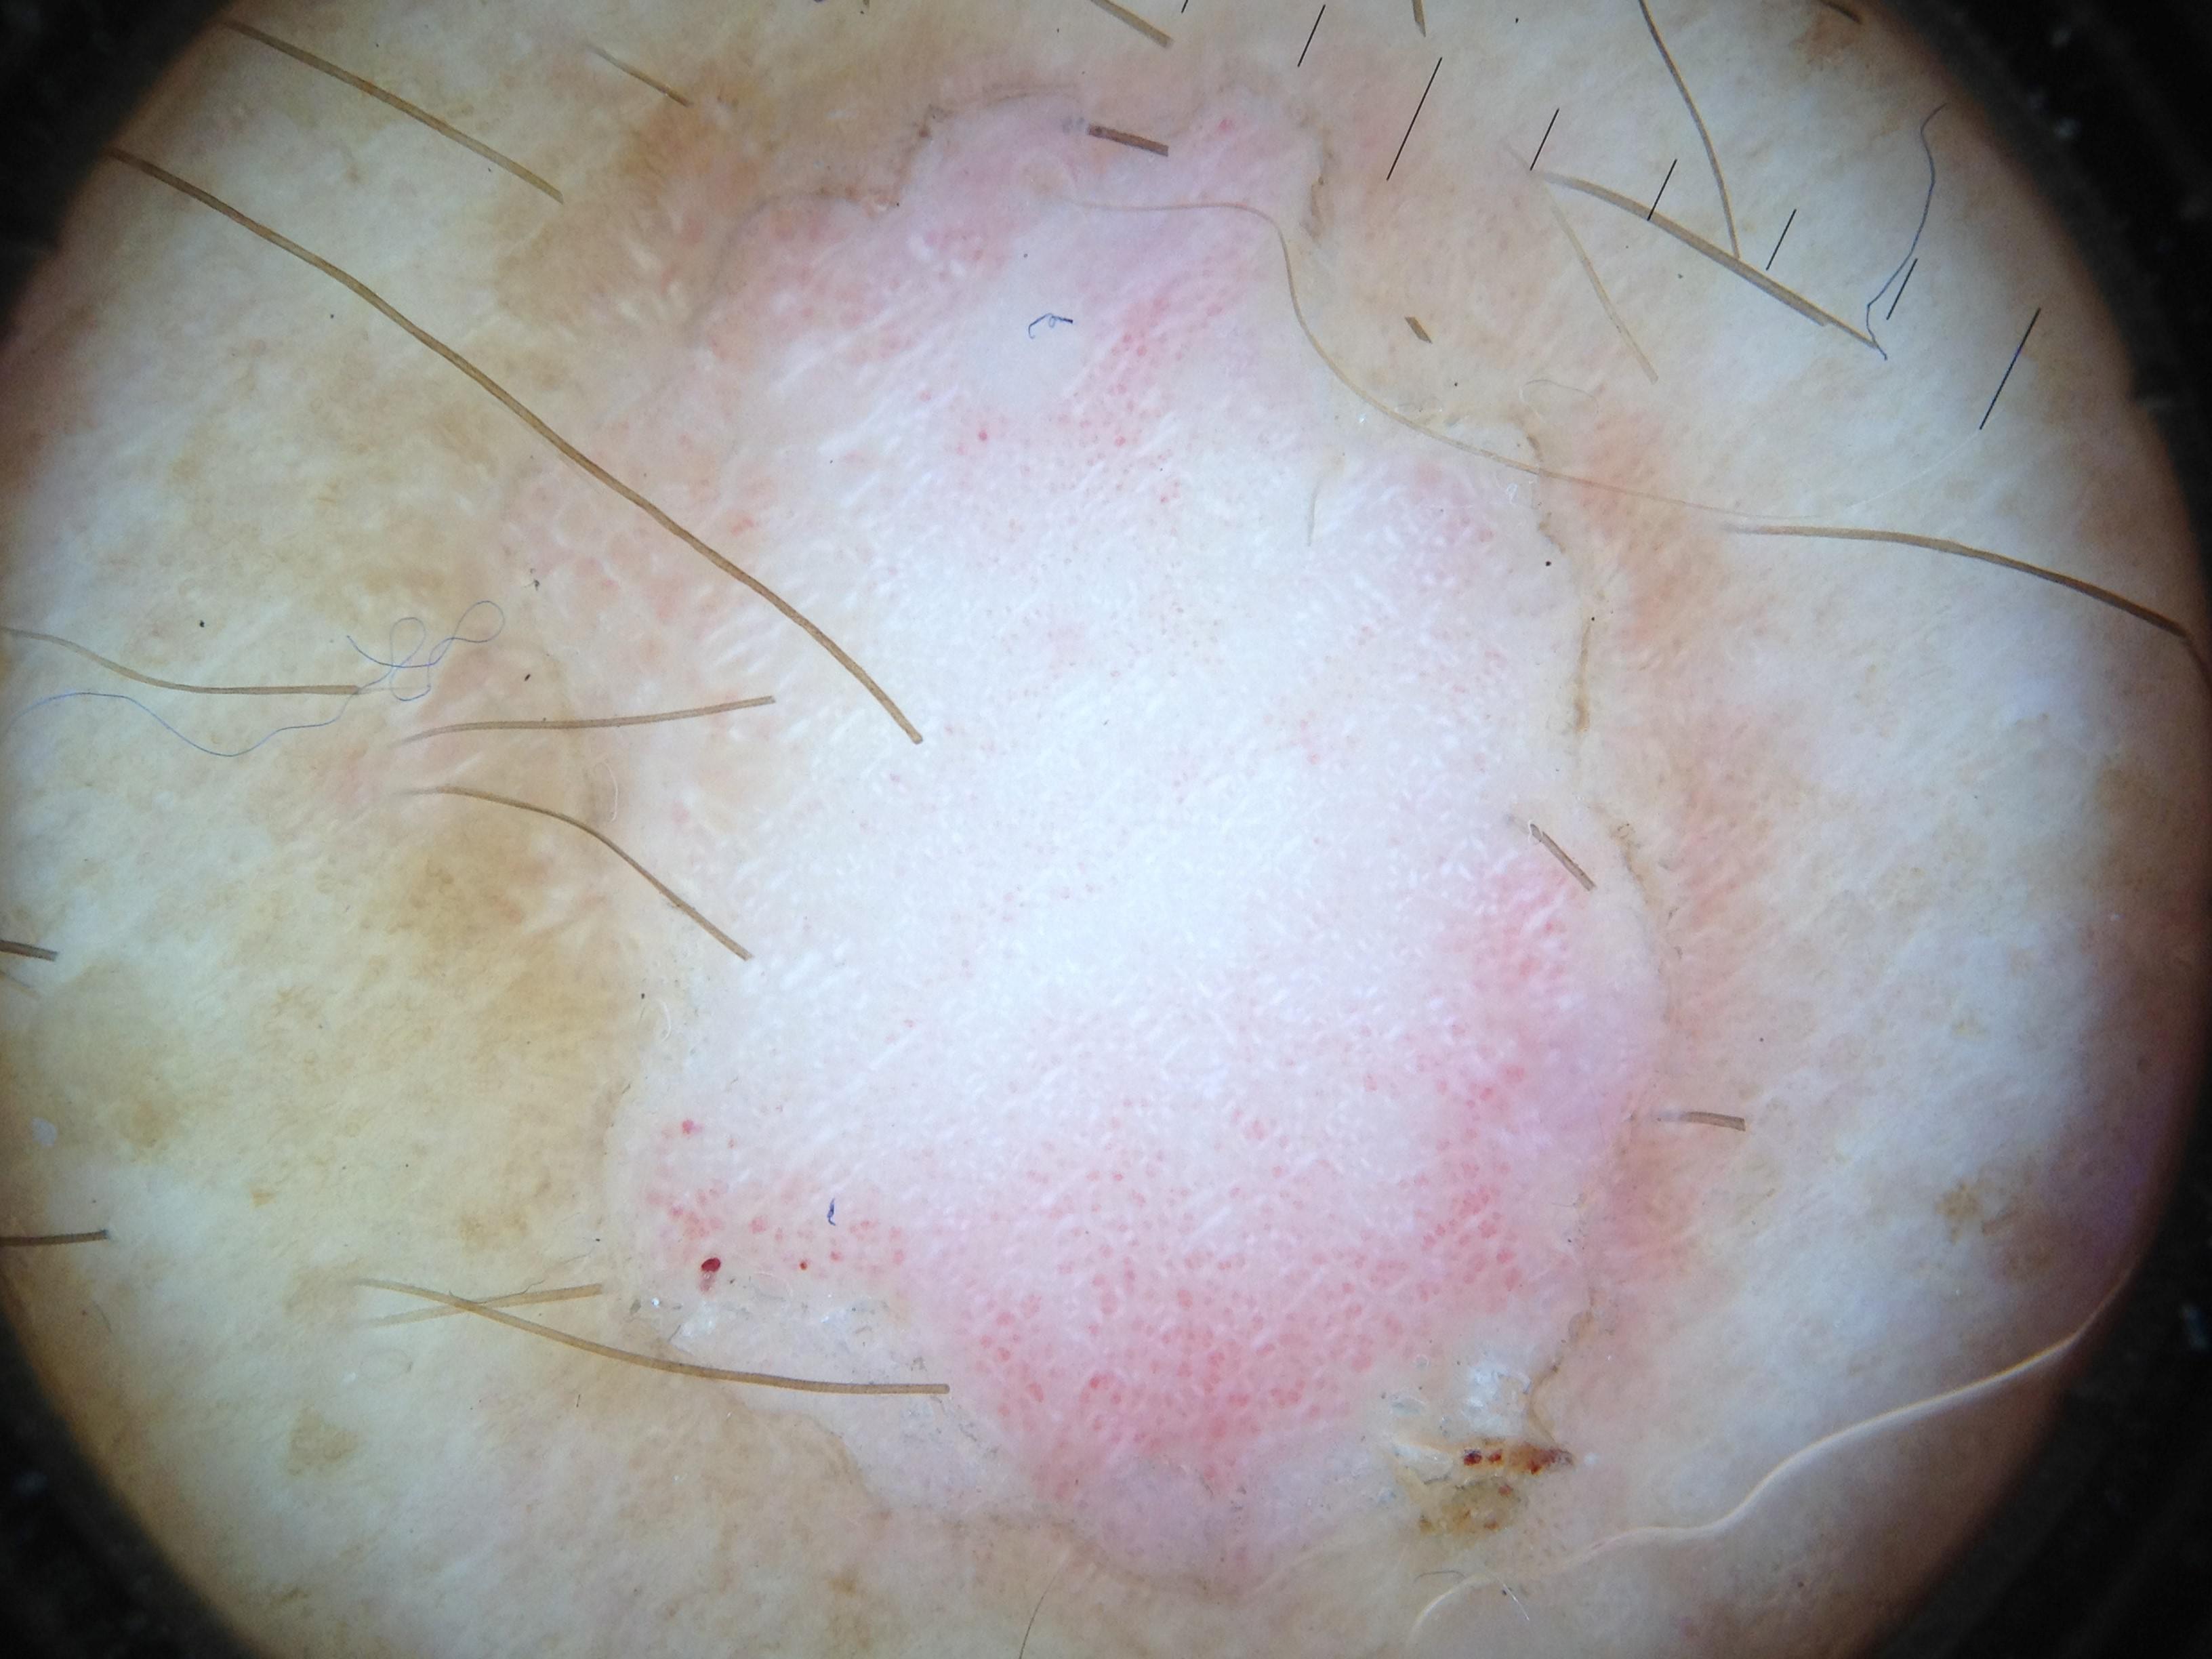

{

"age_approx": 65,

"anatom_site_general": "head/neck",

"concomitant_biopsy": true,

"dermoscopic_type": "non-contact polarized",

"diagnosis_1": "Malignant",

"diagnosis_2": "Malignant epidermal proliferations",

"diagnosis_3": "Squamous cell carcinoma in situ",

"diagnosis_confirm_type": "histopathology",

"family_hx_mm": false,

"image_type": "dermoscopic",

"melanocytic": false,

"patient_id": "IP_2318141",

"personal_hx_mm": false,

"sex": "male"

}